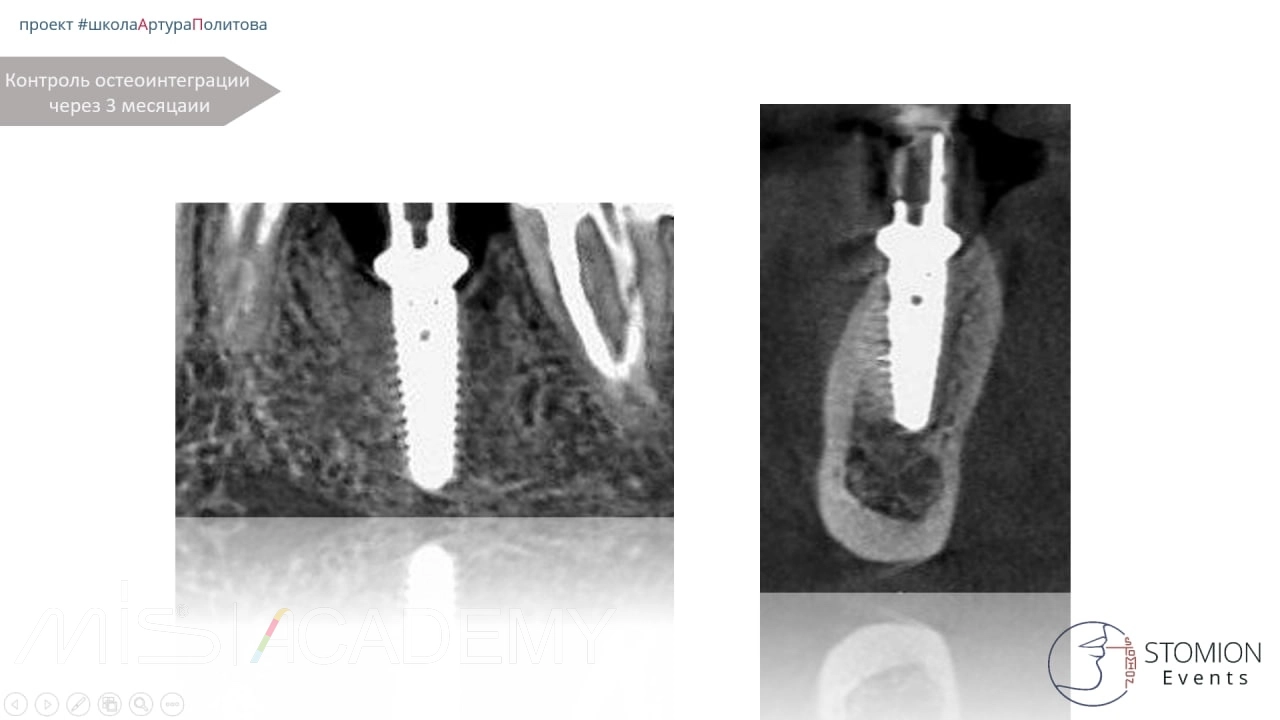

2. Через 3 месяца установлен имплантат MIS C1 размером 3,75 × 11,5 мм.

3. Установлен коннект шириной 5,7 мм, высотой 2 мм.

5. Через 3 месяца проведён контроль интеграции имплантата. Признаки стабильности и остеоинтеграции положительные. Выполнено постоянное протезирование.